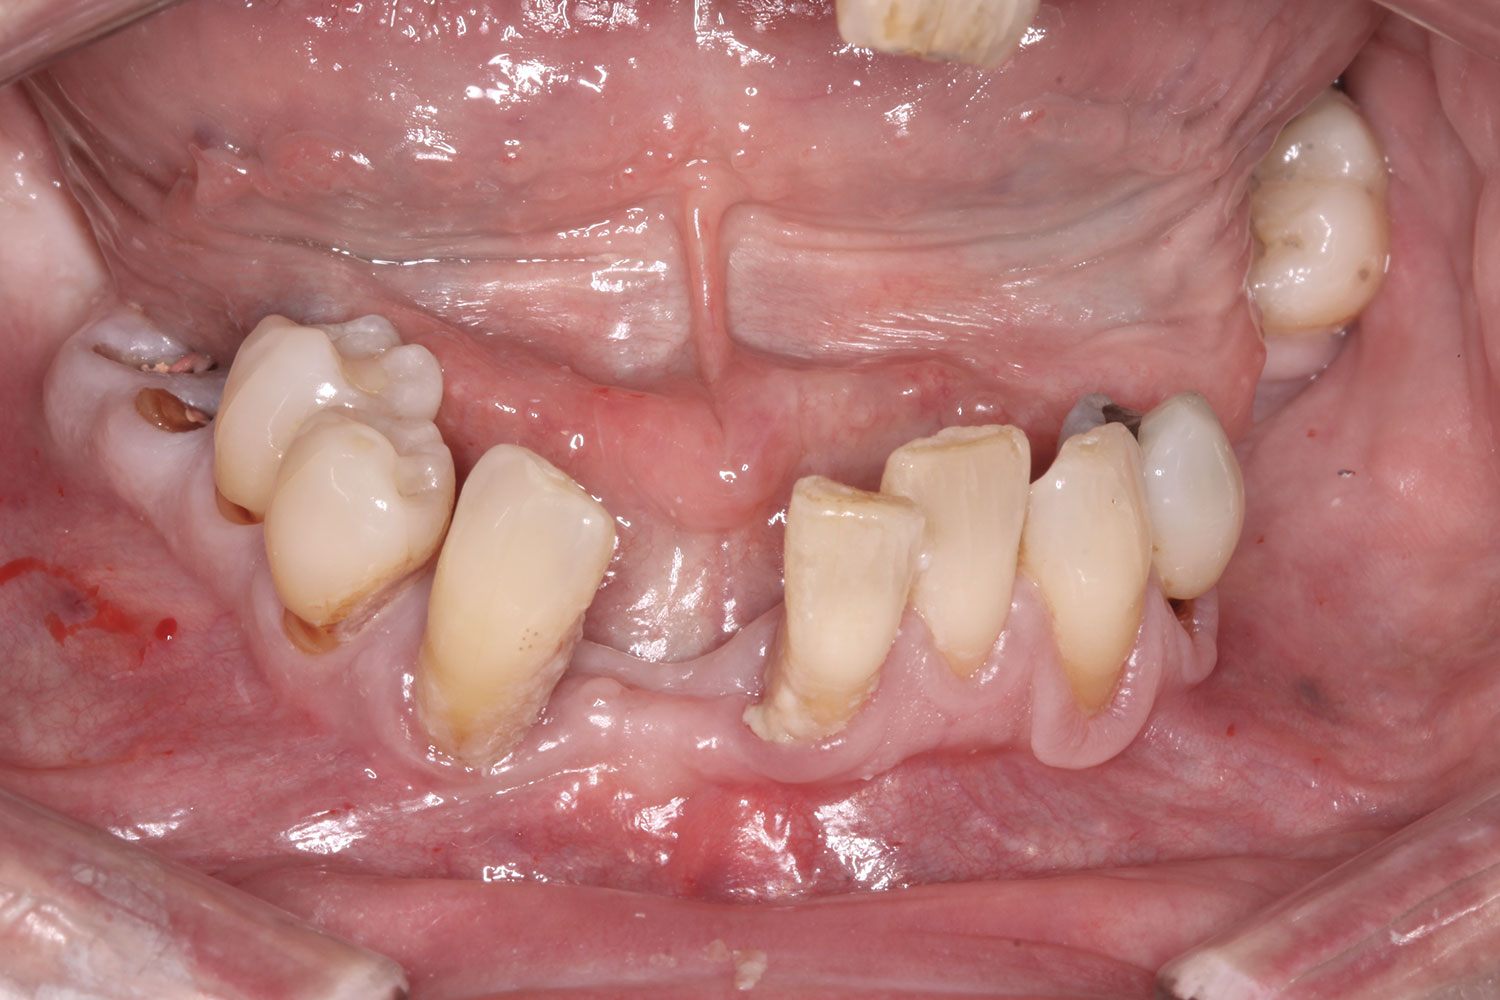

Fig 2. Initial presentation, intraoral view.

Figure 2

A 36-year-old male patient presented with a highly compromised maxillary dentition comprised of only teeth Nos. 4, 6, 7, 9, 10, 11, and 14 (Figure 1 and Figure 2). This poor condition was the result of only sporadic dental care with extractions and no teeth replacements. Soft tissues had normal contour, and bone profiles were generally sustained and favorable. The patient was excited about having the option to transform his compromised esthetics and function in one visit.